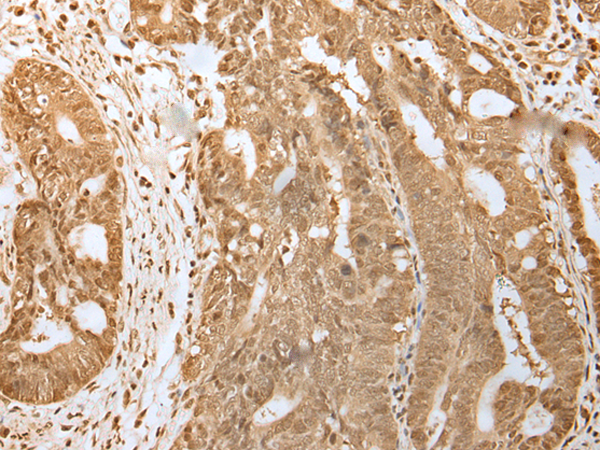

ELISA, IHC |

IHC positive control: |

Human gastric cancer and Human tonsil |

IHC Recommend dilution: |

25-100 |